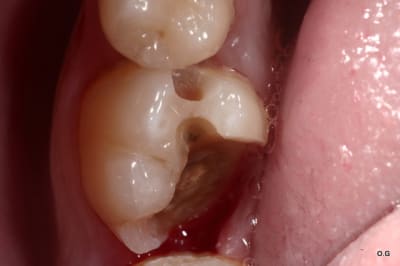

Ben alors j'ai un cas là justement : je fais quoi? Onlay ou Couronne?

Dent vivante, CVI renforcé après la taille en coiffage attente de 3 semaines avec pansement pour être sûr, RAS dent toujours vivante quand je l'ai revu aujourd'hui.

Aujourd'hui : retouche du CVI puis (première photo au stade du mordançage) compo pour le core build-up, pansement.

Les photos sont pas top mais pour le moment je fais avec ce que j'avais sous la main...

Qu'est-ce que je fais pour la suite du coup? Onlay ou Couronne?

PS. On ne voit pas bien la différence à la radio avant-après... Désolé.

Perso je penche pour la couronne...